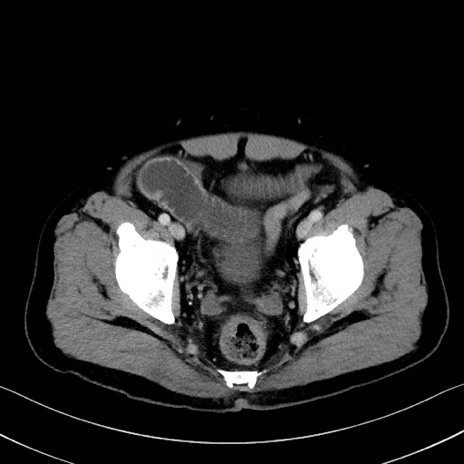

症例35(横断像)

【症例】70歳代 男性

【主訴】腹部膨満、嘔吐

【現病歴】昨日より腹部膨満感出現。本日増悪し、仙痛出現。嘔吐あり、受診。

【既往歴】糖尿病、胆摘後

【身体所見】BP 149/80mmHg、HR 74/min、BT 35.9℃、腹部:膨満、軟、圧痛なし。腸雑音減弱あり。上腹部正中切開瘢痕あり。

【データ】WBC 13500、CRP 1.72